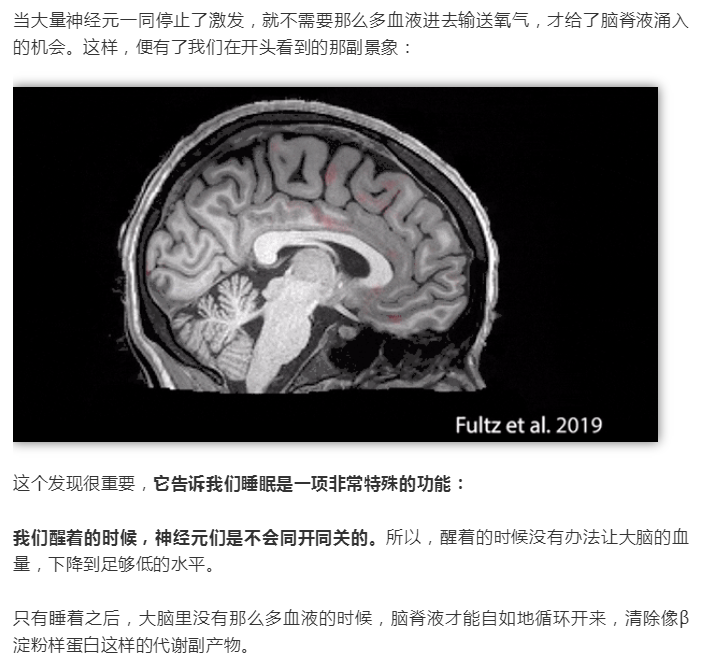

熬夜會(huì)變傻?終于有科學(xué)依據(jù)了